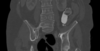

Masculino, 12 anos

Síndrome da sincondrose isquiopúbica assimétrica (Doença de Van Neck-Odelberg)

Variante da normalidade (em geral assintomático)

Crianças

Alargamento e radioluscência na sincondrose isquiopúbica, que simula neoplasias, infecção;